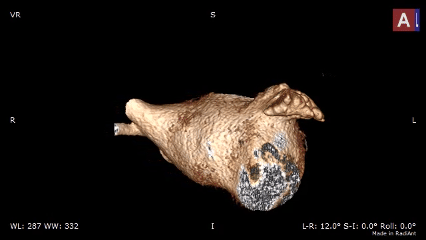

CT三维重建评估

低位菜花型左心耳

该心耳为菜花型左心耳,开口类圆形;

患者左心耳呈多分叶菜花型,开口为类圆形,上下开口不对称,腰部缩窄,远端梳状肌发达,内部空间有限。